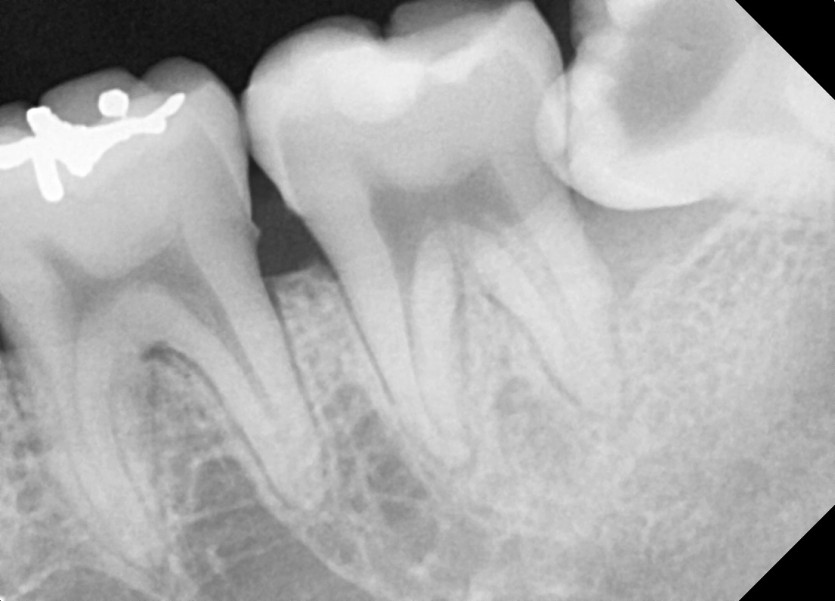

#38 사랑니 발치

구강 외과 전문의가 당일 발치했습니다.